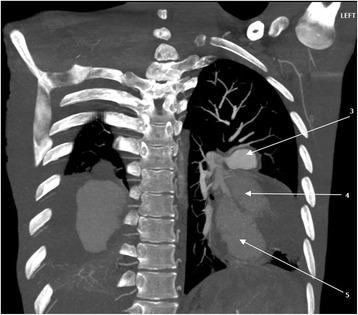

A 24-year-old man, a nursing student of African descent, was referred to us from an up-country regional hospital with a 4-week history of recurrent episodes of breathlessness, awareness of heartbeats and coughing blood 3 weeks after completing a 6-month course of anti-tuberculosis drugs. A physical examination revealed conjuctival and palmar pallor but there were no stigmata of connective tissue disorders, systemic vasculitides or congenital heart disease. An examination of the cardiovascular system revealed accentuated second heart sound (S) with early diastolic (grade 1/6) and holosystolic (grade 2/6) murmurs at the pulmonic and tricuspid areas respectively. Blood tests showed iron deficiency anemia, prolonged bleeding time, and mild hyponatremia. A chest radiograph revealed bilateral ovoid-shaped perihilar opacities while a computed tomography scan showed bilateral multiple pulmonary artery pseudoaneurysms with surrounding hematoma together with adjacent cystic changes, consolidations, and tree-in-bud appearance. Our patient refused to undergo surgery and died of aneurismal rupture after 9 days of hospitalization.

一名24岁的男性,是一名非洲裔护理专业学生,在完成6个月抗结核药物疗程3周后,因反复出现气短、心悸和咯血4周,被一家偏远地区医院转诊至我院。体格检查发现结膜和手掌苍白,但无结缔组织病、系统性血管炎或先天性心脏病的体征。心血管系统检查发现第二心音亢进(S),分别在肺动脉和三尖瓣区有舒张早期(1/6级)和全收缩期(2/6级)杂音。血液检查显示缺铁性贫血、出血时间延长和轻度低钠血症。胸部X线片显示双侧肺门周围椭圆形阴影,而计算机断层扫描显示双侧多发肺动脉假性动脉瘤伴周围血肿,以及相邻的囊性改变、实变和树芽征。我们的患者拒绝接受手术,住院9天后死于动脉瘤破裂。